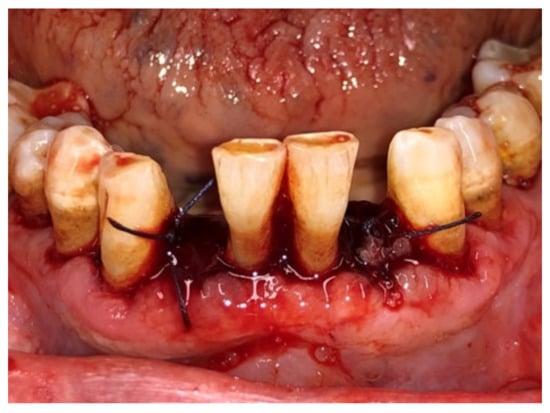

| Tissue colour: | 50% of gingiva red |

| Granulation tissue: | Present | |

| Incision margin: | Not epithelialized, with loss of epithelium beyond incision margin | |

| Suppuration: | Present | |

| Incision margin: | Not epithelialized, with connective tissue exposed | |

| Suppuration: | None | |

| Granulation tissue: | None | |

| Incision margin: | No connective tissue exposed | |

| Tissue colour: | 25% of gingiva red |

| Tissue colour: | All tissues pink |

| Suppuration: | None |